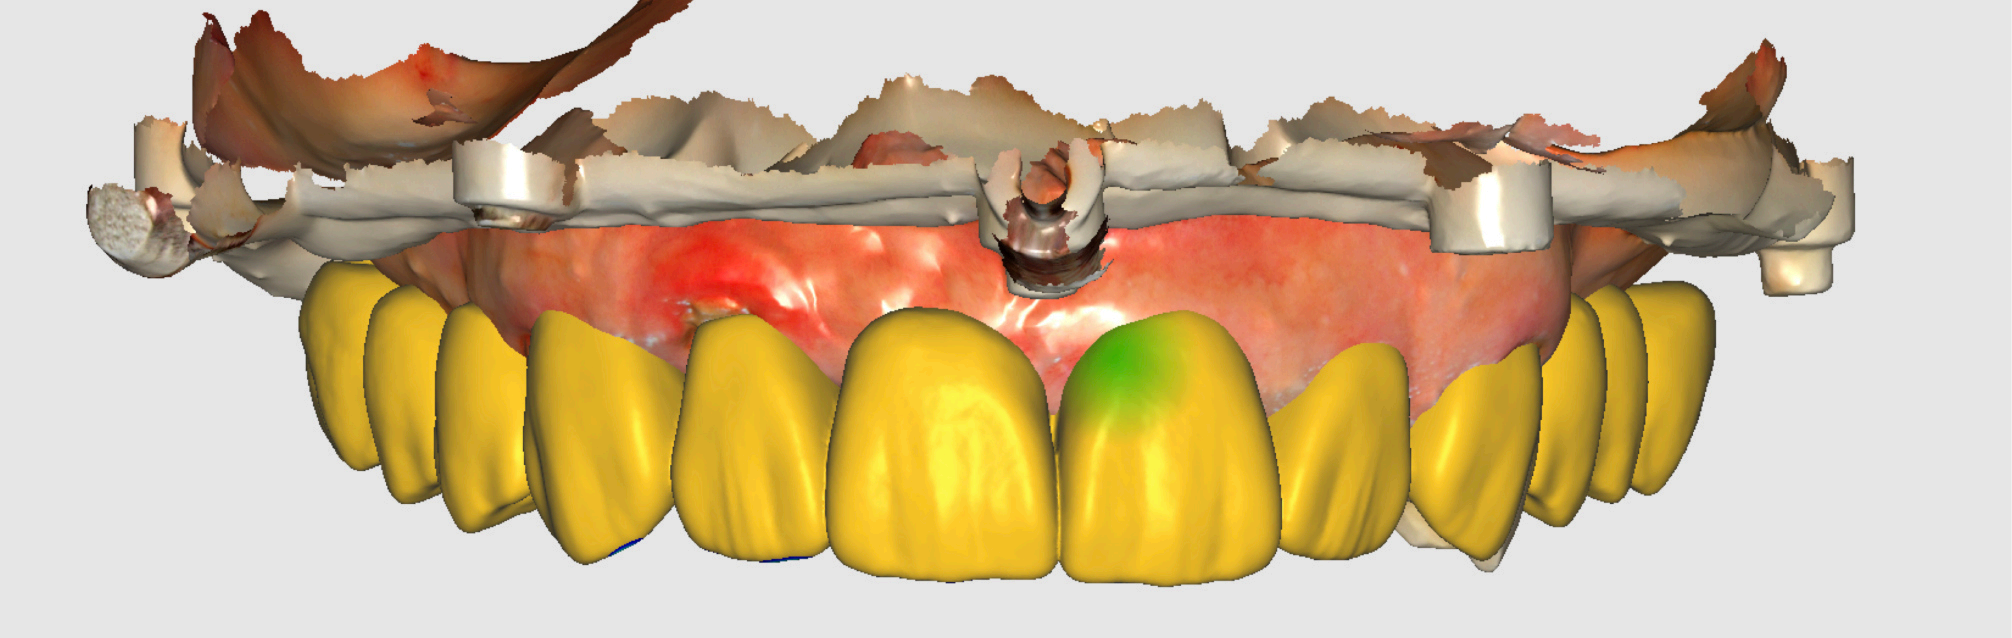

Preoperative and Planning •Fig. 1.1: Frontal intraoral view of the maxilla showing residual roots and fractured teeth. •Fig. 1.2: Occlusal intraoral view highlighting the compromised dentition. •Fig. 1.3: Digital wax-up integrated with a 3D facial scan and smile design guidelines. •Fig. 1.4, 1.5: Visualization of implant positions (16, 14, 12, 22, 24, 26) on a 3D model, prosthetically driven placement. •Fig. 1.6: 3D rendering of the wax-up aligned with the bone level, illustrating bone-prosthesis relationship.

Initial diagnostic workup included a comprehensive radiographic evaluation using cone-beam computed tomography (CBCT) to assess bone volume and quality at the proposed implant sites: 16 (upper right frst molar), 14 (upper right frst premolar), 12 (upper right lateral incisor), 22 (upper left lateral incisor), 24 (upper left frst premolar), and 26 (upper left frst molar). The CBCT confrmed suffcient bone height and width to support six implants without the need for extensive grafting, though minor bone leveling was anticipated. Digital impressions were acquired using the Shining3D Elite intraoral scanner, capturing detailed surface anatomy of the maxilla and remaining teeth. A 3D facial scan was also performed to integrate smile design principles, ensuring the prosthetic outcome aligned with the patient’s facial aesthetics (Fig. 1.3). A digital wax-up was created in Exocad, simulating the fnal prosthesis with attention to tooth proportions, midline alignment, and lip support. After patient approval, this wax-up served as the foundation for implant planning (Fig. 1.4, 1.5).

To optimize implant positioning, the “most apical bone” concept was applied during planning. This approach evaluates the relationship between the prosthetic design and the most apical level of available bone, ensuring that implant placement supports both biomechanical stability and aesthetic outcomes (Fig. 1.6). In this case, the analysis indicated that scalloped bone reduction would be necessary at certain sites to align the bone contour with the planned gingival margin of the FP1 prosthesis. This step was critical to avoid excessive prosthetic bulk and to facilitate a natural emergence profle.